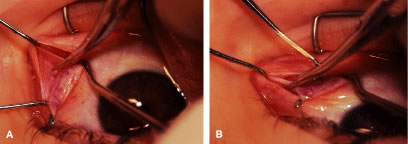

A Stevens' tenotomy hook is passed by the surgeon into the incision and is rotated so that it can be slid underneath the muscle insertion with the tip of the hook held tangential to the globe (Fig. 12). The hook should be passed 2 to 3 mm posterior to the expected location of the muscle insertion. Care is taken not to incorporate intramuscular septum or other adventitial tissue on the hook. When the lateral rectus muscle is secured with the Stevens' or Jameson muscle hook, care should be taken not to bring the inferior oblique muscle up to the insertion (Fig. 13). When the muscle is secured with the Stevens' hook, the hook and the inferior edge of the muscle insertion are elevated and a Jameson muscle hook is passed between the tented muscle tissue and the sclera to secure the muscle at its insertion (Fig. 14). Care is taken to include the entire insertion of the tendon on the hook. The tip of the Jameson hook is gently elevated by depressing the heel of the hook. This maneuver helps to ensure that the entire tendon of the muscle remains captured on the hook. A Stevens' tenotomy hook is placed in the incision, this time anterior to the insertion beneath the conjunctiva (Fig. 15). The Stevens' hook is passed posterior over the orbital surface of the muscle (Fig. 16). Gentle pressure on the Stevens' hook is directed posterior so that the check ligaments and Tenon's tissue that overlie the muscle belly are separated from the muscle capsule with blunt dissection. The hook usually is passed posterior for about 10 mm. When recessing a lateral rectus, attachments between the underside of the lateral rectus and inferior oblique are broken (Fig. 17). Two or three passes over the muscle are made, and, with simultaneous countertraction on the Stevens' hook and the Jameson hook, the conjunctiva is elevated and pulled over the tip of the Jameson hook (Fig. 18A and B).

|

The intermuscular septum and Tenon's capsule at the ball-like tip of the Jameson hook are incised with a Westcott scissors (Fig. 19). A Manhattan forceps can be used to elevate the intramuscular and Tenon's tissue to facilitate this step. Care is taken to incorporate the entire muscle tendon on the Jameson hook before this cut is made. If it is evident that there is residual tendon that is not placed on the hook, the additional tendon, intramuscular septum, and anterior Tenon's tissue are reflected over the tip of the Jameson hook with the closed tips of the Westcott scissors or a small muscle hook.

A Stevens' hook is inserted in the opening in the intermuscular septum created by the scissors and is passed anterior to the insertion. Parks has referred to this maneuver as the “pole test.” This maneuver is done to verify that the tendon of the muscle has not been split and that the complete muscle tendon is incorporated on the hook. Leaving residual slips of muscle tendon will partially or completely negate the effect of a recession procedure (Fig. 20A and B).

The anterior Tenon's capsule is cut free from the muscle insertion by grasping the loose tissue anterior to the insertion of the tendon with a forceps and gently tenting it (Fig. 21A and B). Care is taken not to grasp muscle capsule or muscle tendon fibers in the forceps. To best accomplish this step, the blunt tipped Westcott scissors is placed perpendicular to the globe. Cleaning the tissue anterior to the muscle permits passing the needle accurately through the rectus muscle tendon with unobstructed visualization. If the capsule of the muscle tendon is cut, the tendon may split. Two small Stevens' hooks are used to elevate the conjunctiva and expose the intermuscular septa and the tissue overlying the muscle capsule. These tissue bands are cut with the Westcott scissors (Fig. 22A and B). Care is taken not to cut into the muscle or the capsule of the muscle (Fig. 23). The intermuscular septa can be cut 3 to 4 mm back for recessions and 5 to 9 mm back for resections.42